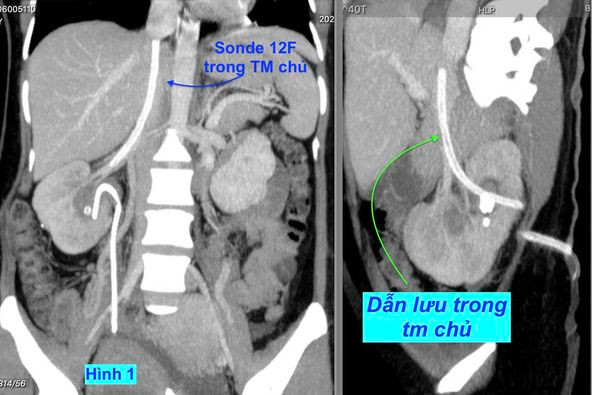

Một bệnh nhân được chuyển đến Bệnh viện Đại học Y Hà nội từ một bệnh viện lân cận với sự cố vô cùng hy hữu: dẫn lưu thận nhưng không hiểu vì lý do gì mà sonde dẫn lưu thay vì vào bể thận thì nó nằm trong tĩnh mạch chủ bụng rồi đi ngược lên trên theo chiều tĩnh mạch vào đến sát tim. (hình 1).

| Hình 1 |

Qua phân tích phim chụp, nhóm hội chẩn đã xác định đây là biến chứng “kép”: sonde dẫn lưu xuyên qua động mạch gây giả phình động mạch thận đồng thời xé rách tĩnh mạch thận để chui vào tĩnh mạch chủ dưới đi lên thêm khoảng 20 cm đến sát tim.